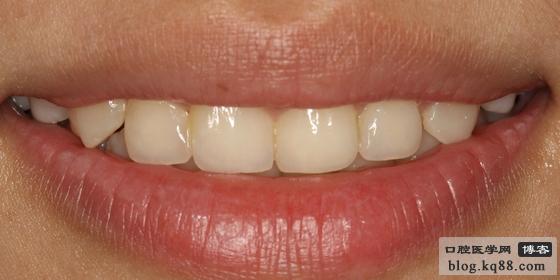

選用D6樹脂(選用4種樹脂)進(jìn)行修復(fù),此圖為打磨拋光后的即刻照片

一星期后的效果(微笑)樹脂有個(gè)過度的時(shí)期。